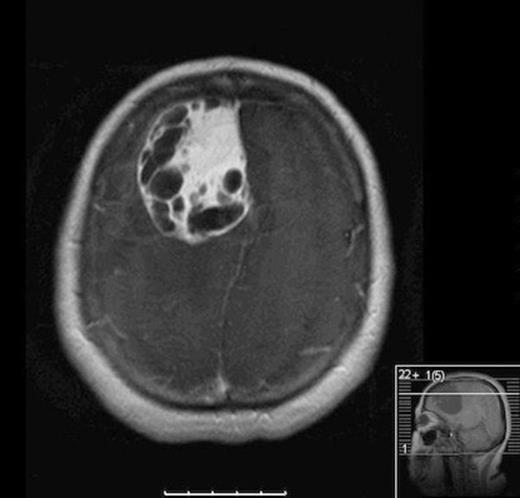

Our patient is a forty-nine year-old Native American female with a two-month history of progressively worsening headaches along with gait instability. She reported falling to the left side quite often. She presented to an outside hospital where CT scan of the head showed a large right frontal hypodense mass with significant vasogenic edema and twenty millimeters of left to right midline shift. She was transferred to University of New Mexico Medical Center where MRI of the brain demonstrated a 6.5 cm x 5 cm heterogeneously enhancing cystic and solid mass with significant vasogenic edema and midline shift (Fig 1). Her haematocrit was within normal limits at 40. Family history was negative for von Hippel Lindau Syndrome. VHL Genetic workup was negative and CT abdomen was negative for other lesions.

Axial MRI with contrast showing heterogenous enhancing solid and cystic component of tumor